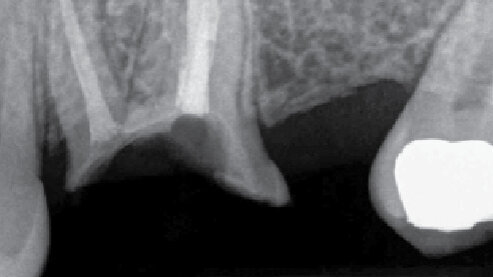

Pacient s nevýznamnou anamnézou byl do mojí praxe doporučen proto, abych zhodnotil zub 26. Pacient neměl potíže, zub byl endodonticky léčen praktickým stomatologem přibližně sedm měsíců před konzultací a nebyl dosud postendodonticky rekonstruován. Klinicky jevil známky rozsáhlé kariézní destrukce, hloubka sondáže 3 mm, do dutiny ústní byl exponován kořenový výplňový materiál a zub nebyl ani dočasně dostavěn. Na rentgenovém snímku nebyl patrný periapikální nález a množství kosti okolo zubu bylo adekvátní (obr. 1).

Prvním krokem byla exkavace kariézních tkání při 4,5násobném zvětšení s přídavným osvětlením z náhlavního světla v absolutně suchém prostředí zajištěném kofferdamem, což bylo nutné ke zjištění množství zbývajících zubních tkání. Na základě klinického zjištění a rentgenového snímku (obr. 2) bylo konstatováno následující:

a) Dno dřeňové dutiny bylo příliš slabé

b) Riziko perforace bylo velice vysoké

c) Periradikulární dentin byl nedostatečně silný, aby udržel definitivní rekonstrukci